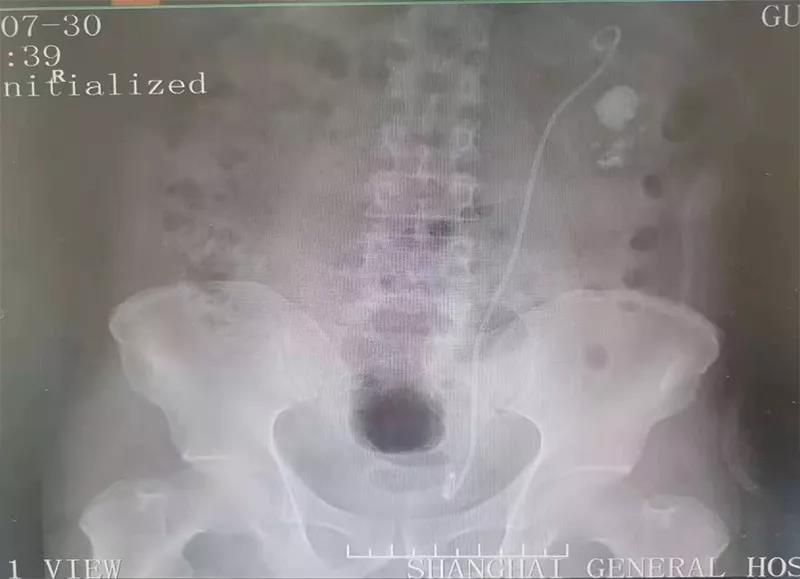

患者,男性,56岁。因左侧腰背部酸胀不适于1月前入院治疗,ctu示:左侧肾脏部分鹿角型结石,大小约31*18mm,左肾积水。于2019年7月26号行左输尿管软镜下取石术。现为进一步治疗左肾结石,收治入院。

2019年6月3日本院CTU:左侧肾盂输尿管交界处结石,左肾积水。双肾多发结石。双肾囊肿。

左肾盂输尿管交界处结石,左肾积水,双肾结石,双肾囊肿,高血压病,冠心病,双侧输尿管结石手术史

CTU:左肾盂输尿管移行段结石,其上尿路中重度积水,双肾旋转不良。